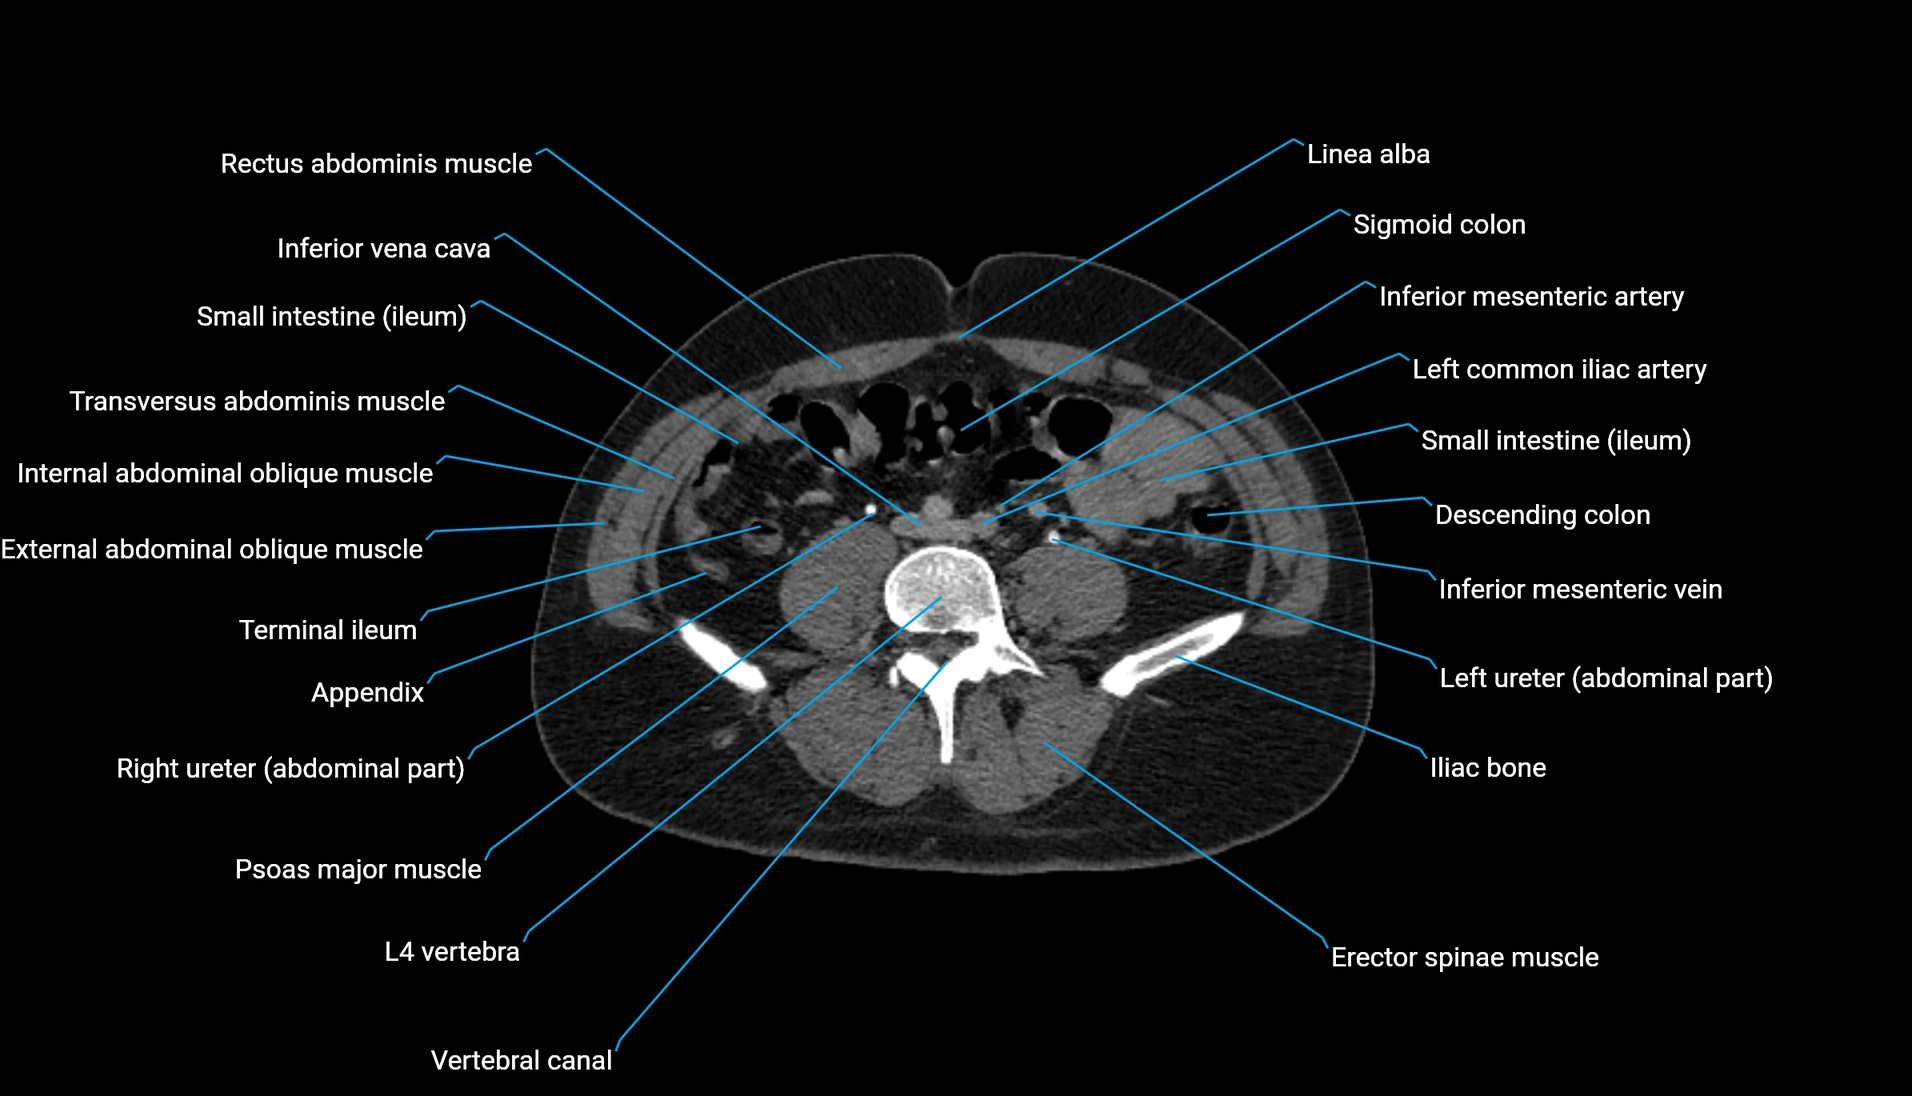

CT Appearance

Non-contrast CT:

-

Demonstrates cortical bone of acetabular rim in excellent detail

Detects fractures, dysplasia, retroversion, or bony overcoverage (pincer impingement)

3D reconstructions used in preoperative hip surgery planning

CT VRT 3D image

CT image